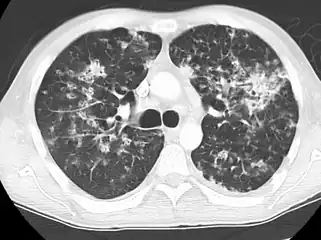

Miliary tuberculosis is a form of tuberculosis that is characterized by a wide dissemination into the human body and by the tiny size of the lesions (1–5 mm). Its name comes from a distinctive pattern seen on a chest radiograph of many tiny spots distributed throughout the lung fields with the appearance similar to millet seeds—thus the term "miliary" tuberculosis. Miliary TB may infect any number of organs, including the lungs, liver, and spleen.[2] Miliary tuberculosis is present in about 2% of all reported cases of tuberculosis and accounts for up to 20% of all extra-pulmonary tuberculosis cases.[3]

Testing for miliary tuberculosis is conducted in a similar manner as for other forms of tuberculosis, although a number of tests must be conducted on a patient to confirm diagnosis.[4] Tests include chest x-ray, sputum culture, bronchoscopy, open lung biopsy, head CT/MRI, blood cultures, fundoscopy, and electrocardiography.[10] The tuberculosis (TB) blood test, also called an Interferon Gamma Release Assay or IGRA, is a way to diagnose latent TB. A variety of neurological complications have been noted in miliary tuberculosis patients—tuberculous meningitis and cerebral tuberculomas being the most frequent. However, a majority of patients improve following antituberculous treatment. Rarely lymphangitic spread of lung cancer could mimic miliary pattern of tuberculosis on regular chest X-ray. [15]